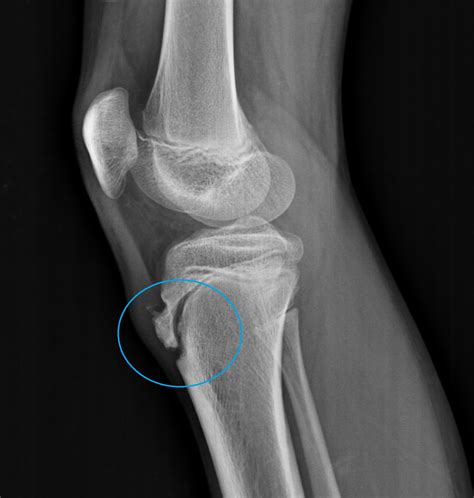

osgood-schlatter disease exercises Osgood schlatters schlatter physio ...